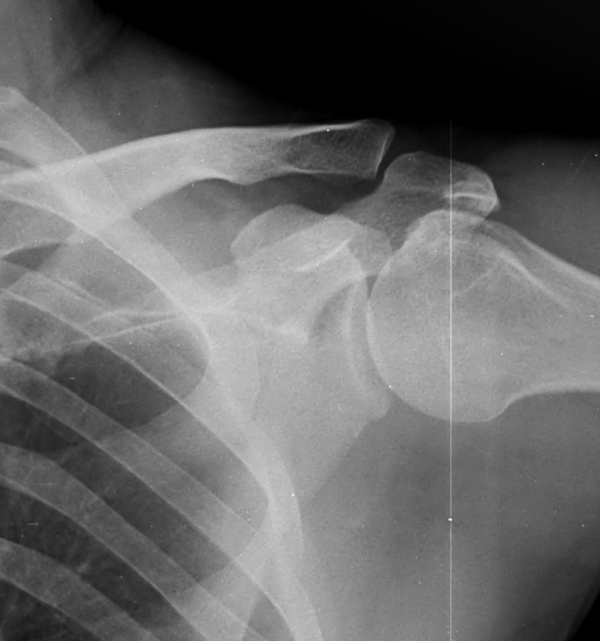

ƯÀÌ °ßºÀ ¾Æ·§¸éÀÇ °æÈ­ ¼Ò°ß ¹× °ßºÀ ¾Æ·¡ ¿¹¸®ÇÑ °ñ±ØÀÌ °üÂûµÊ

¹æ»ç¼±»çÁøÀ̳ª ÀÚ±â°ø¸í°Ë»ç¿¡¼­ °ñ±ØÀÌ °üÂûµÇ°í ±Ø»ó°Ç ÆÄ¿­ÀÌ ÀÖ´Â °æ¿ì °Ë»ç¿¡¼­ º¸ÀÌ´Â

°ñ±ØÀÌ ±Ø»ç°ÇÆÄ¿­ÀÇ ¿øÀÎÀ̶ó°í ÃßÁ¤ÇÒ ¼öµµ ÀÖ´Ù.  ±×·¯³ª ±Ø»ó°ÇÆÄ¿­ÀÌ Ç¥Ãþº¸´Ù´Â ½ÉÃþ¿¡¼­

´õ ¸¹ÀÌ ¹ß»ýÇϰí Áõ»óÀ» ÀÏÀ¸Å°Áö ¾Ê´Â °ñ±ØÀÌ ¸¹Àº Á¡À» °í·ÁÇÒ ¶§ °Ë»ç¿¡¼­ º¸ÀÌ´Â °ñ±ØÀ»

Ä¡·á(°ßºÀ¼ºÇü¼ú)ÀÇ ´ë»óÀ¸·Î ÇÏ´Â °ÍÀº Çϸ®ÀûÀÎ °áÁ¤ÀÌ ¾Æ´Ï´Ù. ÀÌ È¯ÀÚÀÇ °æ¿ìó·³ ±Ø»ó°Ç